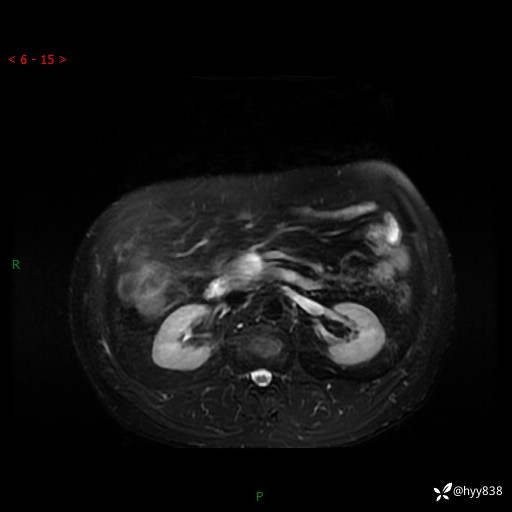

MRI(T1WI+T2WIfs+DWI)

增强